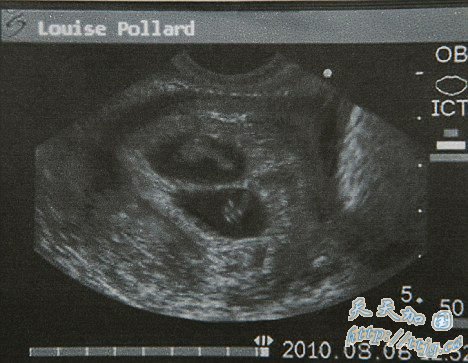

超声波显示,路易丝·博拉德已经怀孕8周,而且怀的是一对双胞胎

据英国《每日邮报》8日报道,近日,路易丝在曼彻斯特一家私人诊所做了孕期检查。超声波显示,她已经怀孕8周,而且怀的是一对双胞胎。早在6月上旬,路易丝被曝为本·拉登儿子奥马尔及其英国妻子扎娜(原名简·菲利克斯布朗)代孕生子。